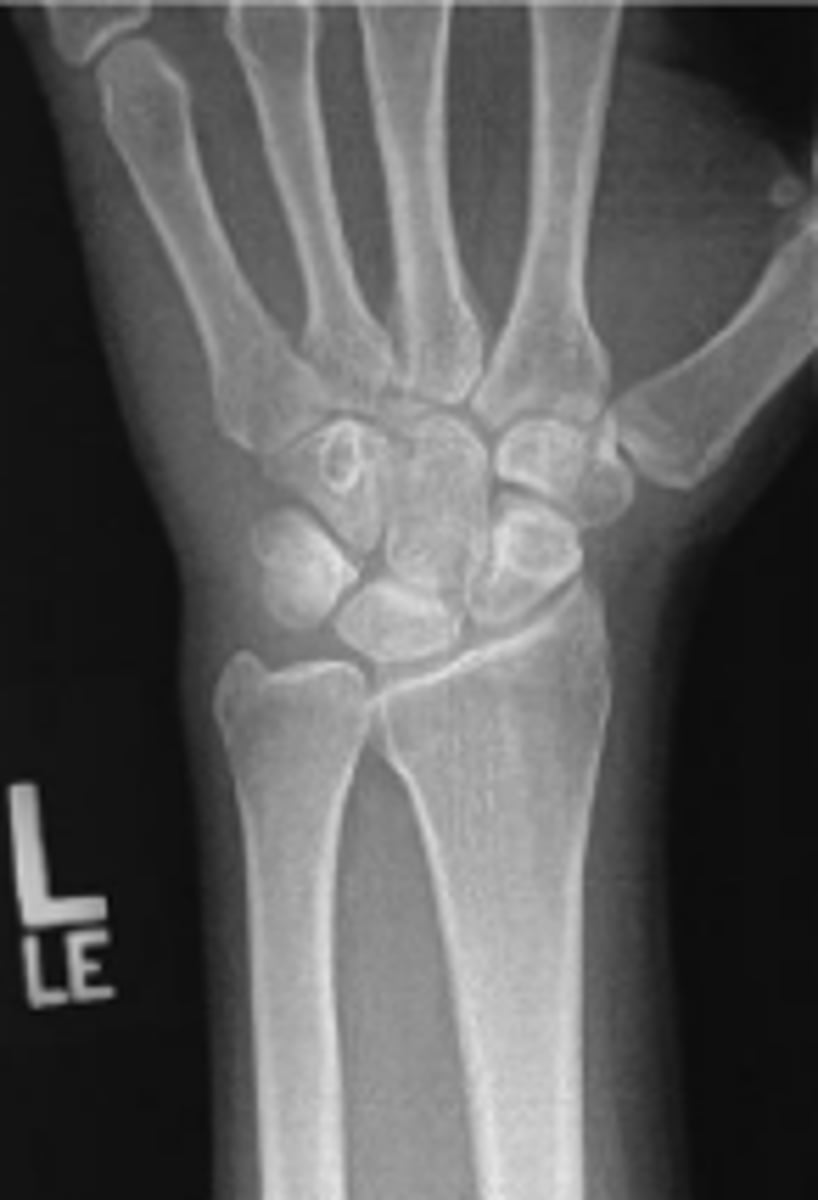

PA of the left wrist

What is the name of the radiographic view?